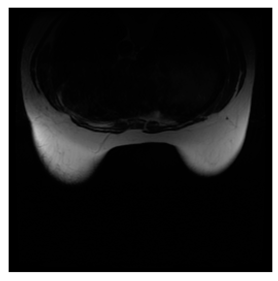

Breast-MRI-NACT-Pilot is an MRI-type image database, collecting breast medical images of 64 patients. Some samples are shown in Figure 12a.

Figure 12.

Sampled images in the tested benchmark databases: (a) Breast-MRI-NACT-Pilot (breast), (b) ACRIN-DSC-MR-Brain (brain), (c) NIH (chest), (d) Lung-PET-CT-Dx (lung), (e) Prostate-MRI (prostate), and (f) Other grayscale standard images.